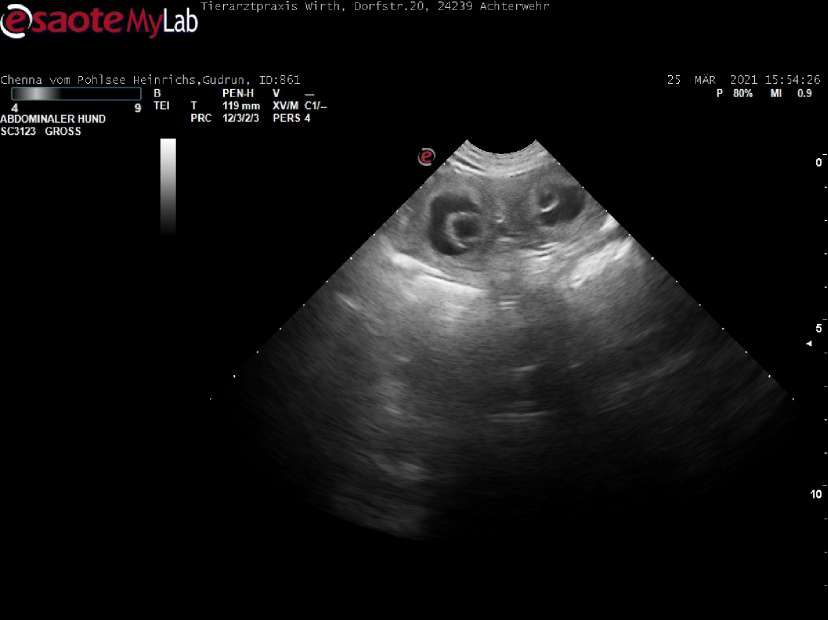

Und gesehen haben wir sie auch schon. Hier auf dem Foto, das sind nicht die Augen von einem Monster, sondern zwei von den die klitzekleinen G-lies in ihren schwarzen Fruchtblasen.